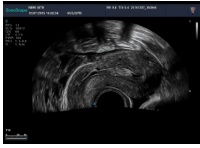

腔內(nèi)探頭,具有頻率高,圖像分辨率高等特點,不需充盈膀胱,探頭緊貼受檢部位,使盆腔器官處于聲束的近場區(qū)域,圖像更清晰。